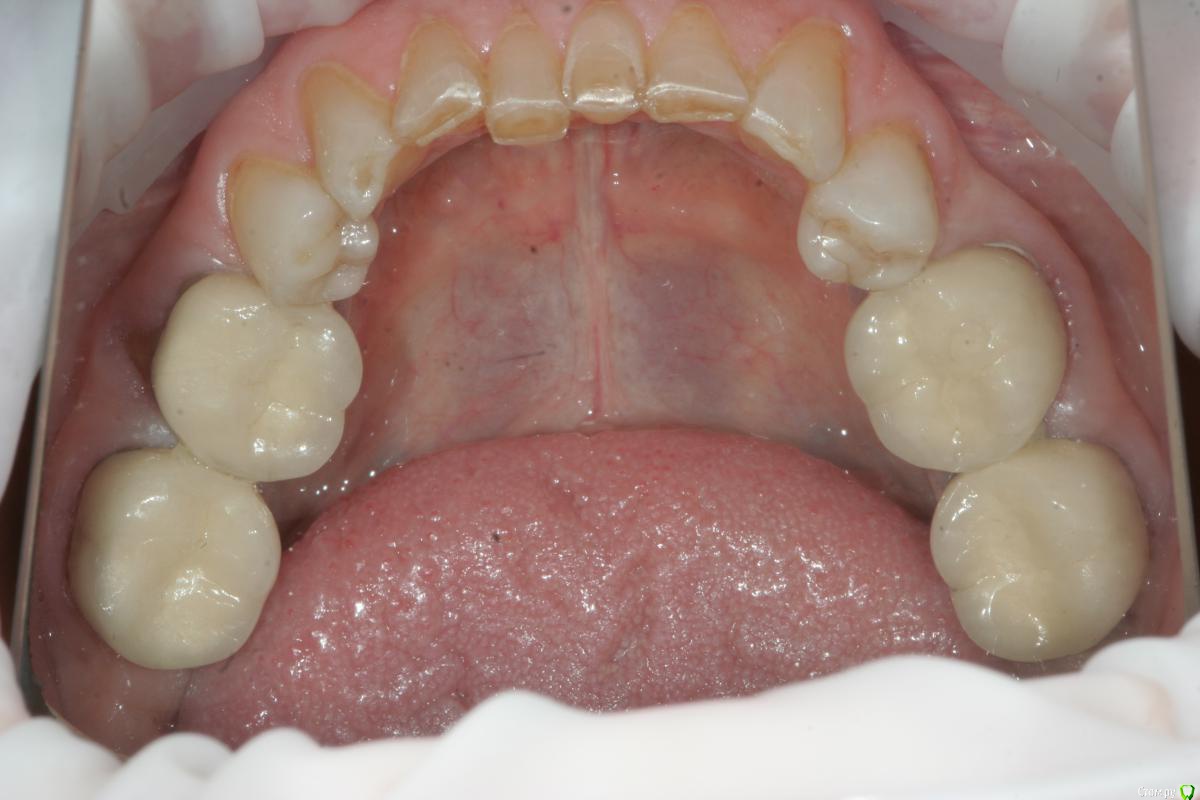

Lolopop Опубликовано 17 марта, 2015 Поделиться Опубликовано 17 марта, 2015 меня больше интересует какого состояние зубов под золотыми коронками - обязательно сфотографируйте - наверник там все отлично , а сколько лет реставрации на передних зубах? Ссылка на комментарий

togrul Опубликовано 18 марта, 2015 Автор Поделиться Опубликовано 18 марта, 2015 Вот еще фото лица. По бюджету нет ограничений ( мк на золоте, Емах). Провести снятие, эндо, воск, временные, перио нужно , но хирург не планирует ( по определенным причинам). Если делать перио во фронте какая методика было бы наиболее оптимальным в данной ситуации?Начал снимать коронки им 20 лет, под ними все очень даже не плохо) высота нижнего отдела лица снижена на сколько пока не готов ответить. модели будут Ссылка на комментарий

togrul Опубликовано 5 сентября, 2015 Автор Поделиться Опубликовано 5 сентября, 2015 Прошу прощение за качество фото. Ссылка на комментарий